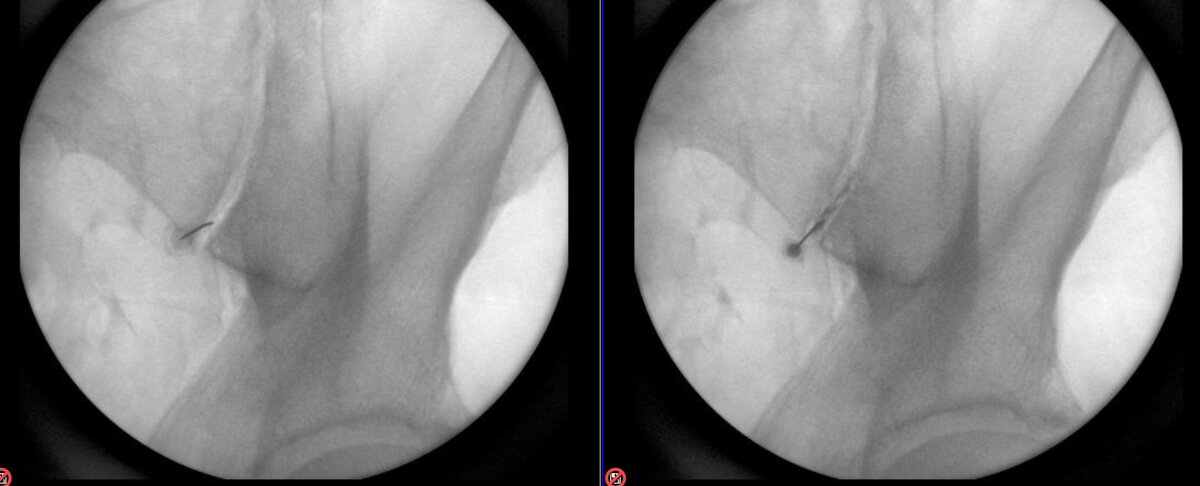

A few more from today. Picture on right good example of anterior, posterior, and inferior joint capsule contrast flow. Ignore the superior needle on the picture on right (or not) ... had a Bertolotti joint injection attempt.